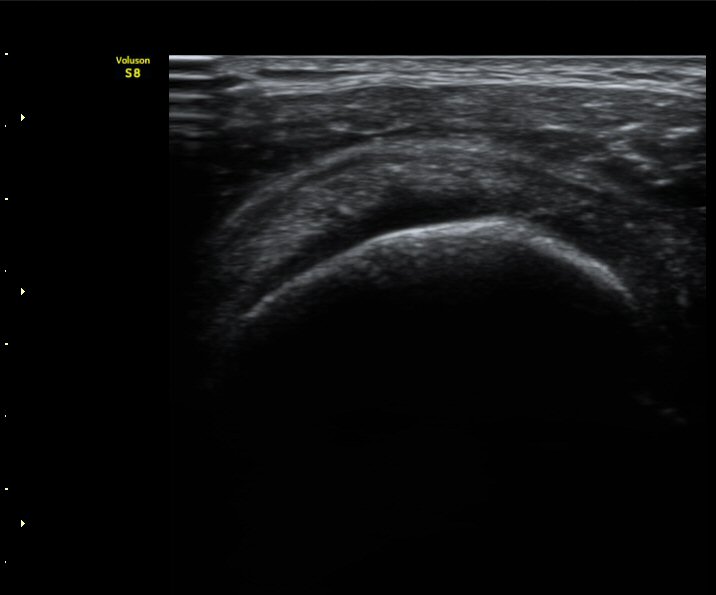

3°³¿ù ÈÄ ÃßÀû°Ë»ç

2049205267_d4912430_US181205109.jpg